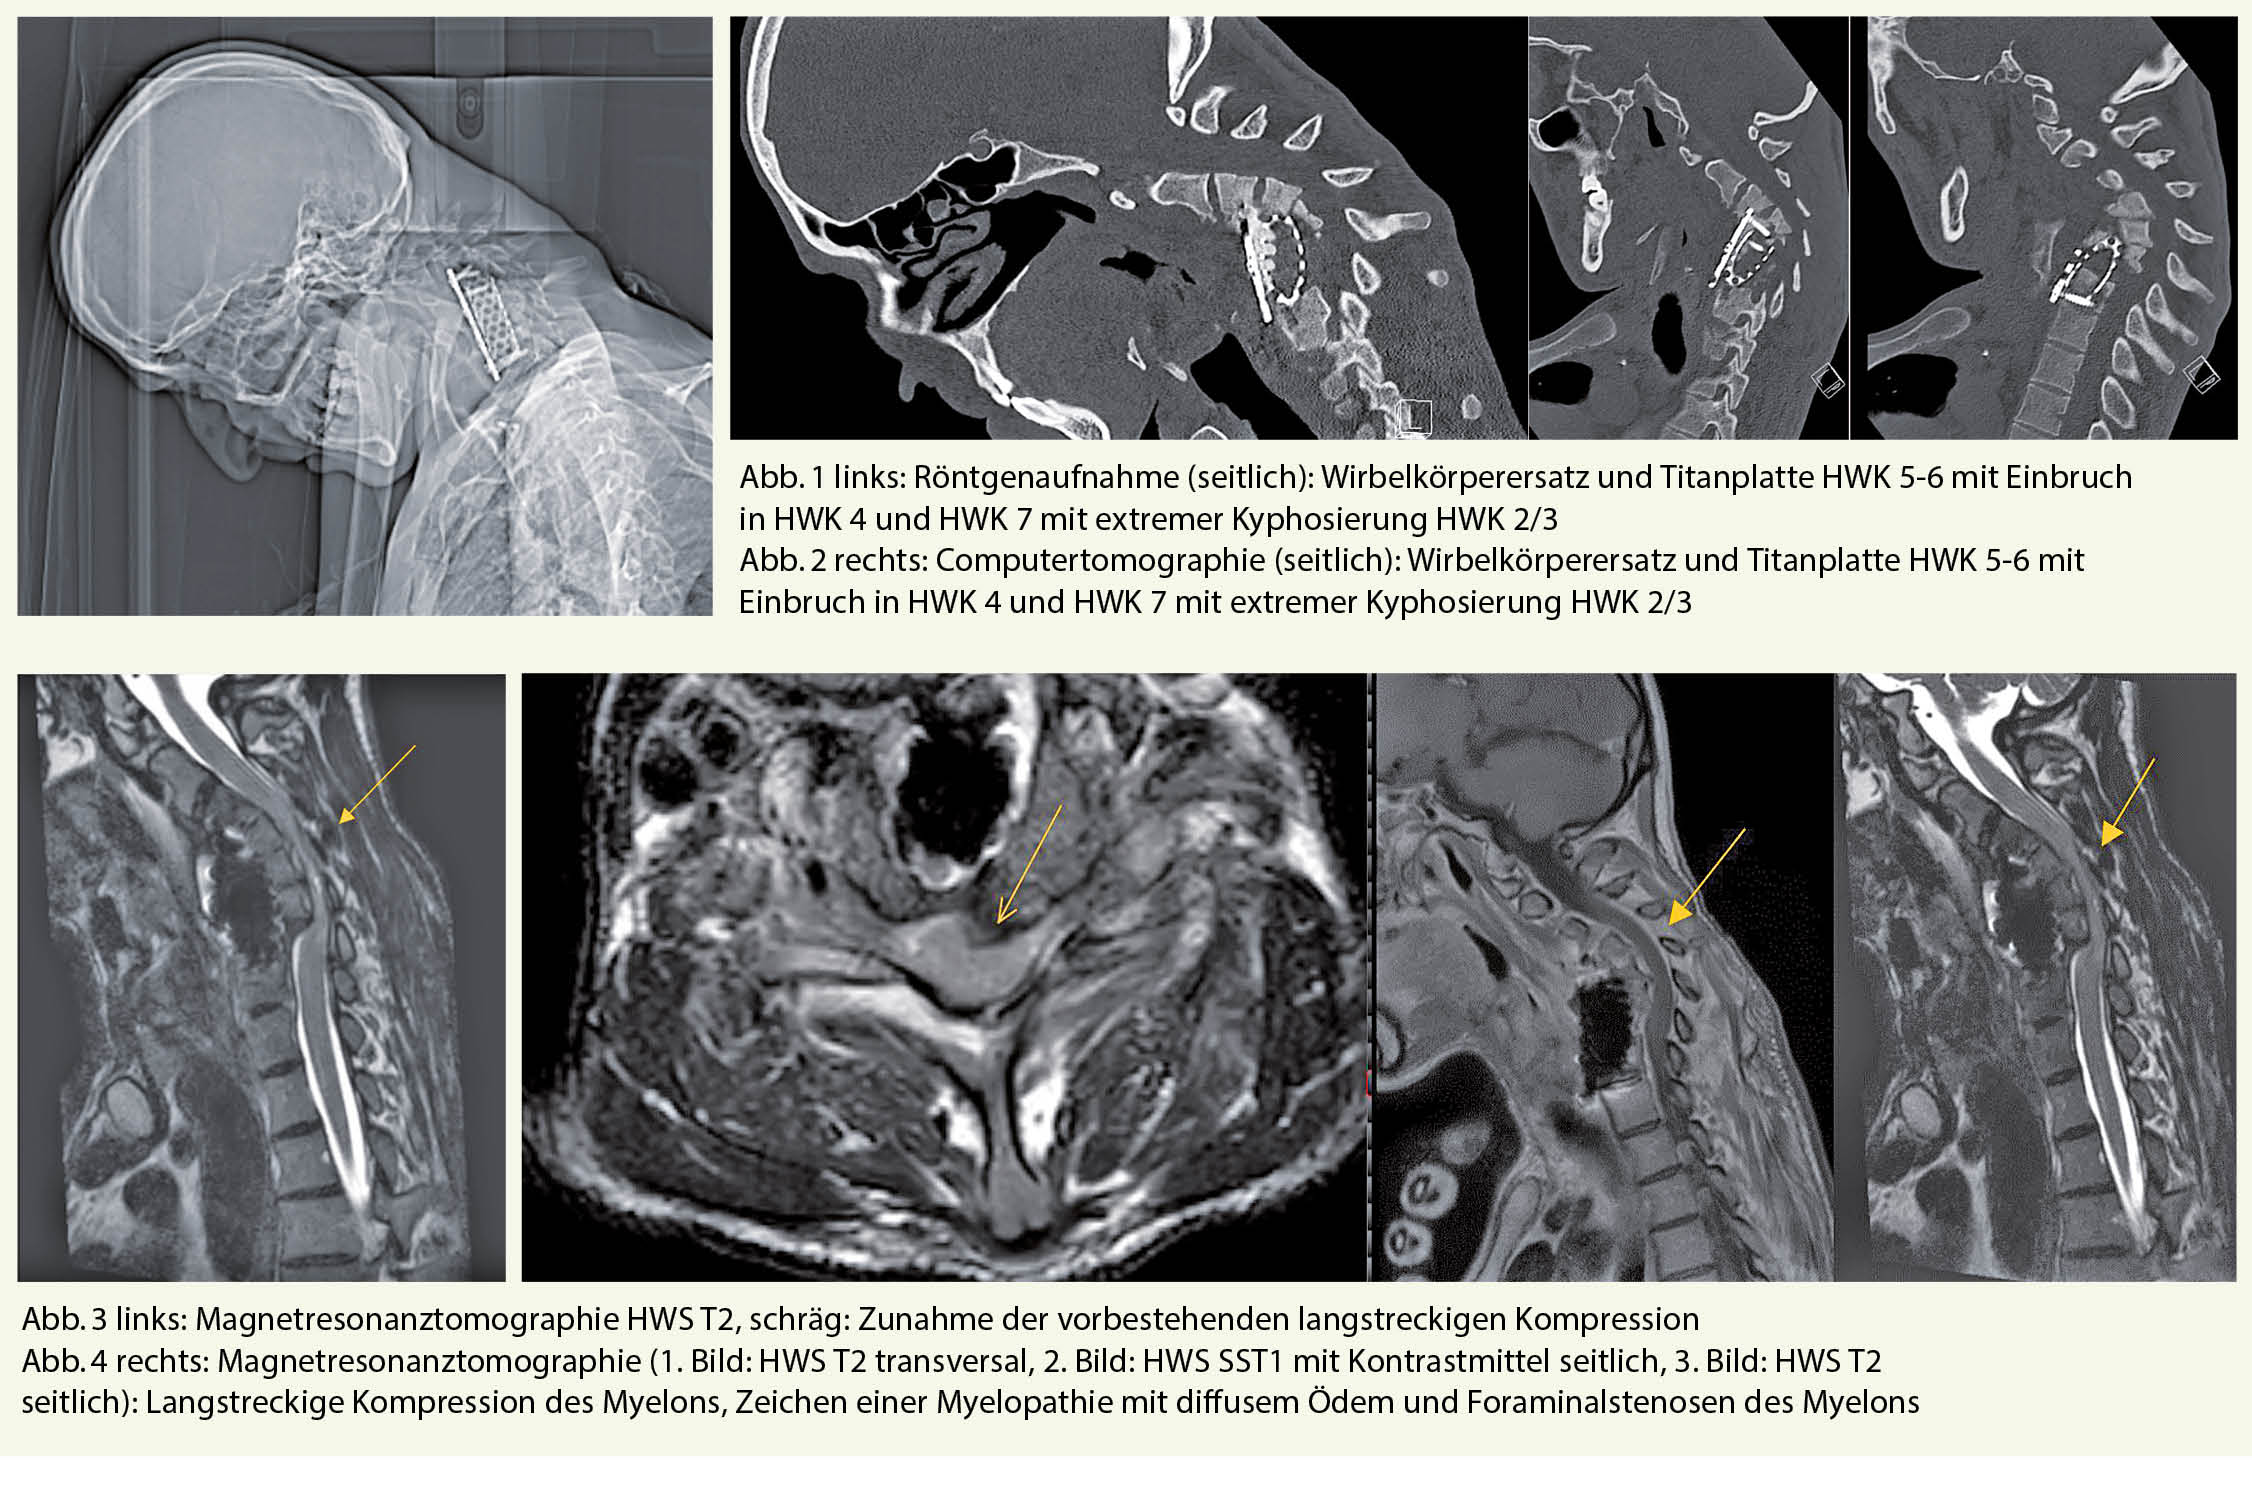

Daraus resultierte eine instabile Fraktur der Halswirbelkörper (HWK) 6 und 7 mit einhergehender neurologischer Ausfallsymptomatik. Zunächst erfolgte keine adäquate Behandlung, was zur Folge hatte, dass sich die neurologischen Symptome weiter verschlechterten. Nach acht Monaten musste der inzwischen rollstuhlgängige Patient schliesslich in seinem Herkunftsland notfallmässig operiert werden. Die chirurgische Versorgung erfolgte mittels Korporektomie von HWK 5 und 6, sowie durch einen Wirbelkörperersatz aus Titan (Mesh-Körbchen) von HWK 4 bis HWK 7 (Abb. 1). Unmittelbar postoperativ zeigte sich ein komplikationsloser Verlauf (3). Gemäss Patientenangaben konnte er seinen Kopf gerade halten und wieder selbständig gehen. Nach vier Wochen kam es jedoch zu einer postoperativen Kyphosierung mit massiver Schmerzexazerbation. Die ausgeprägte Deformität führte zu einer kompletten Unselbstständigkeit (4, 5).

In der initial durchgeführten Computertomographie (CT) wurde eine Instabilität im Bereich der HWS diagnostiziert (Abb. 2). In der darauffolgenden Magnetresonanztomographie (MRI) zeigte sich eine leicht progrediente Anterolisthesis von HWK4 bei vorbestehender langstreckiger Kompression des Myelons mit Zeichen einer Myelopathie sowie diffusem Ödem. Eine Lockerung des Osteosynthesematerials konnte zwar nicht eindeutig nachgewiesen werden (Abb. 3), was eine solche naturgemäss nicht ausschliesst, jedoch wurde der Verdacht einer aus dem Implantat ausgehenden Spondylodiszitis gestellt (Abb. 4).